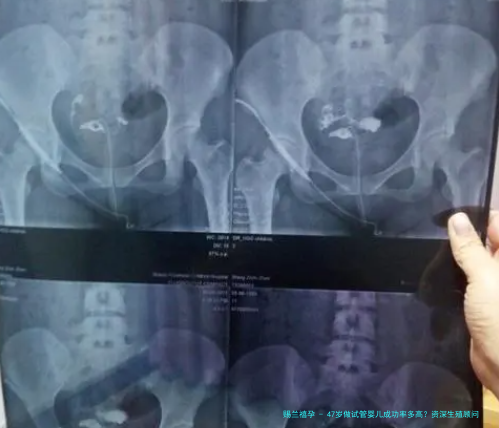

1. 卵巢功能衰弱:卵子“存货告急”

女性出生时卵泡数量已牢固,47岁时卵巢储存通常严重枯竭,窦卵泡数量可能仅存个位数,促排后获卵子数少少,乃至可能出现“空卵泡综合征”。临床显示,此岁数段的单周期取卵子数常不足5枚,远低当年轻女性的15-20枚。